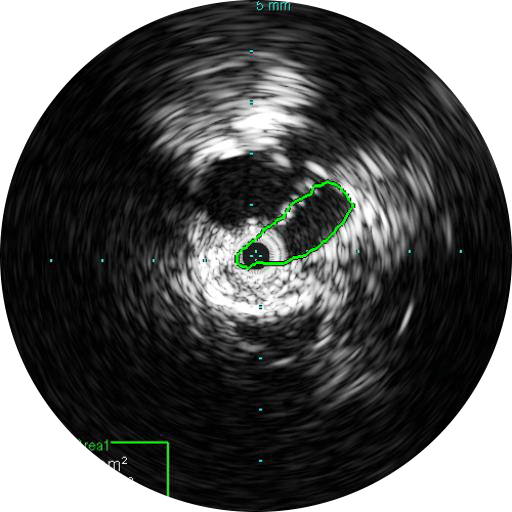

Визуализация на 360 ̊ способствует лучшему пониманию заболевания и придаточных структур, к которым также относятся уровень компрессии, остеофиты, тромбы и прочее.

Цифровой катетер для ВСУЗИ Visions PV (0,035 дюйма) дополняет стандартные инструменты проведения ангиографических процедур, обеспечивая оценку морфологии кровеносных сосудов и их визуализацию в поперечном сечении. Благодаря рабочей длине, равной 90 см, и максимальному диаметру визуализации, равному 60 мм, для инвазивных процедур с использованием проводника диаметром 0,035 дюйма, устройство облегчает диагностику заболеваний вен и периферических артерий и помогает врачам выбрать правильный подход к лечению с учетом индивидуальных потребностей пациента.